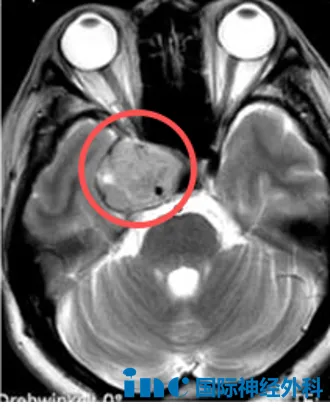

3、26岁女孩右侧丘脑病变

还有一名女孩芝芝,右侧丘脑病变,大小约25mm×23mm×24mm,虽然无明显临床症状,但这个此前已经经历过鞍区生殖细胞瘤放化疗的年轻女性来说,这一次她希望手术可以快刀斩乱麻,为她切除这个丘脑病变。“对我来说是常规手术。”面对面咨询时,巴教授的自信也让她对这次手术充满信心。